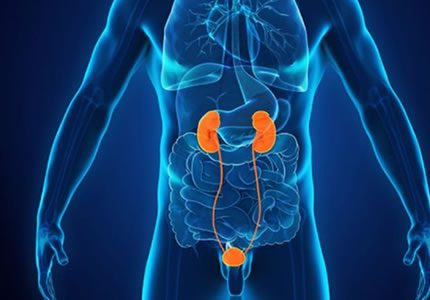

Renal & Urinary Tract

- A comprehensive evaluation of both kidneys to screen for stones, cysts, and structural anomalies. It is an essential investigation for recurrent urinary tract infections (UTIs), "flank" (side) pain, or changes in kidney function.

- £150

- Ideal for: Side pain, recurrent UTIs, and monitoring kidney health.

- We assess the thickness of the bladder wall and check how well the bladder empties after use (post-void residual). This is particularly useful for investigating symptoms like a frequent urge to go or a feeling of incomplete emptying.

- £100

- Ideal for: Urinary retention, frequent infections, and bladder function checks.